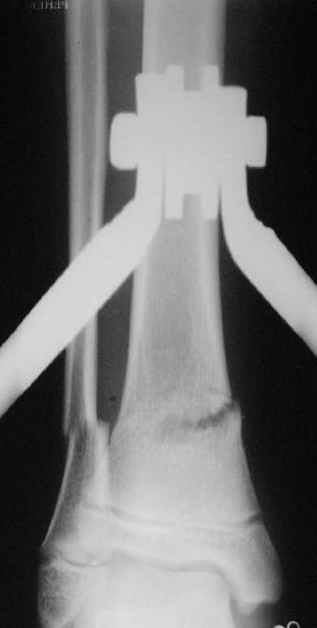

Фиксация

в гипсе